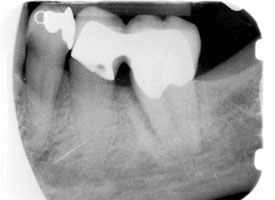

> nachher

Durch eine systematische Parodontalbehandlung und einem kleinen Eingriff, um den Knochen an dieser Stelle aufzubauen, konnte der Knochendefekt ganz eliminiert werden und dadurch der Zahn erhalten werden.